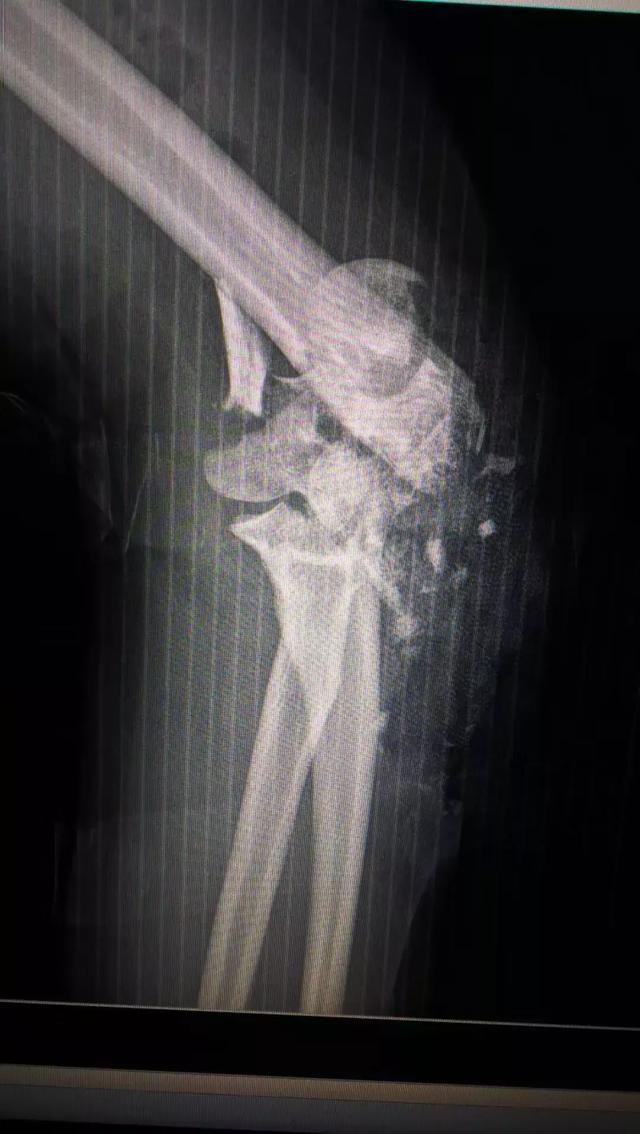

故事发生在去年夏天,高考完的第一天,从急诊科收治来一位年轻女性伤员,左侧肘关节开放性粉碎性骨折合并血管伤,关节接近毁损。虽然张主任对这类伤有较丰富的经验,但当时医院刚开业半年,新的骨科团队面临一些挑战。迫于伤员病情急重,必须立即手术不能耽搁,伤员家属也予以充分的信任。

于是,张主任带领团队凌晨急诊给她做了肘部扩创、血管神经肌腱关节囊探查修复、局部皮瓣转移、肱骨骨折尺骨骨折切开复位内固定+骨折外固定关节外固定架固定、食指近节指骨骨折內固定术。此类手术需要医生极为细致与耐心,还要在术中不断地评估决策,为伤员的短期与长期利益抉择出最佳方案。

.术前术后对比图

此次家属专程前来表示感谢,并告知她女儿术后恢复良好,没耽误学业,顺利走入心仪的大学校园。术后复查得到了洛阳正骨医院的高度肯定:得益于圣德骨科一期手术的及时、有效,完整的保住了关节的功能,为二期康复打下了非常好的基础!